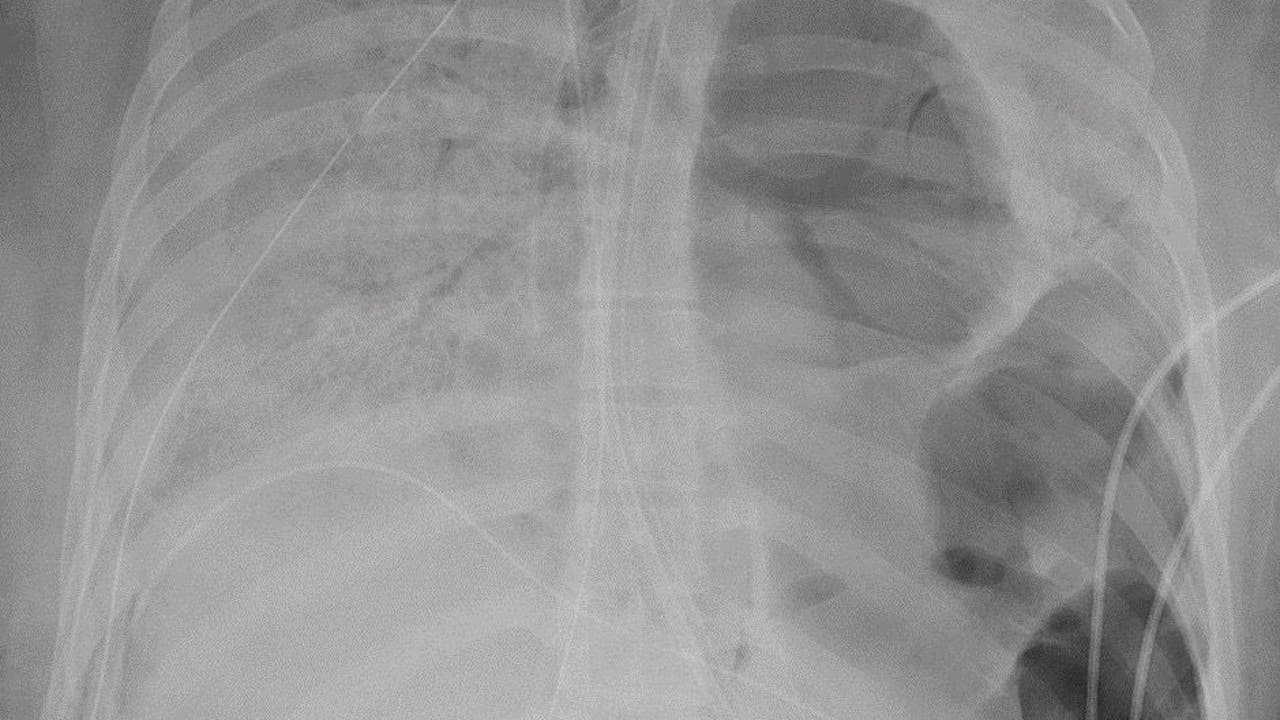

Doctors said the COVID-19 patient, identified as a woman in her 20s, was otherwise pretty healthy. An X-ray of her lungs are pictured in a provided image. (Photo credit: Northwestern Memorial Hospital)

Bharat performed the operation and said the 10-hour procedure was challenging because the virus had left her lungs full of holes and almost fused to the chest wall.